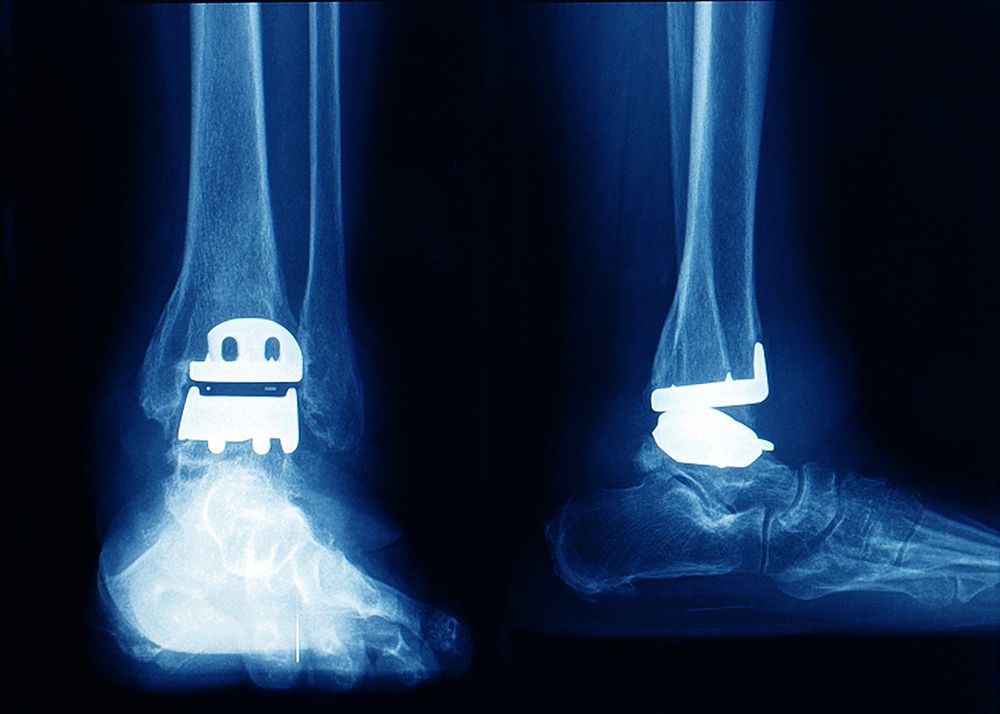

Ankle arthritis often develops after trauma or years of wear, when the cartilage that cushions the joint wears down. This bone-on-bone contact leads to swelling, stiffness, and pain that can severely limit mobility. The

MoveWright™ Total Ankle Replacement replaces the damaged joint surfaces with a customized implant that mimics the natural motion of a healthy ankle—allowing for flexibility and movement that traditional fusion surgery cannot provide.